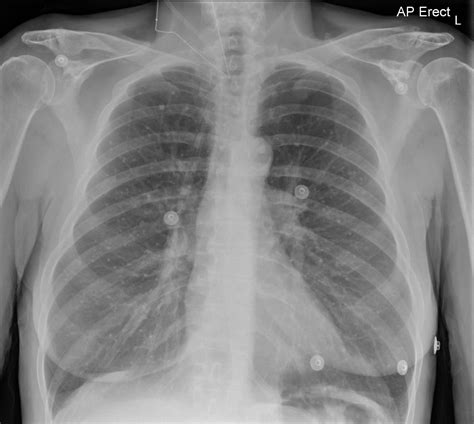

• Chest X-ray: A chest X-ray can reveal the presence of calcium deposits in the lungs.

• CT Scan: A computed tomography (CT) scan provides detailed images of the lungs and can help identify the location and extent of the calcification.